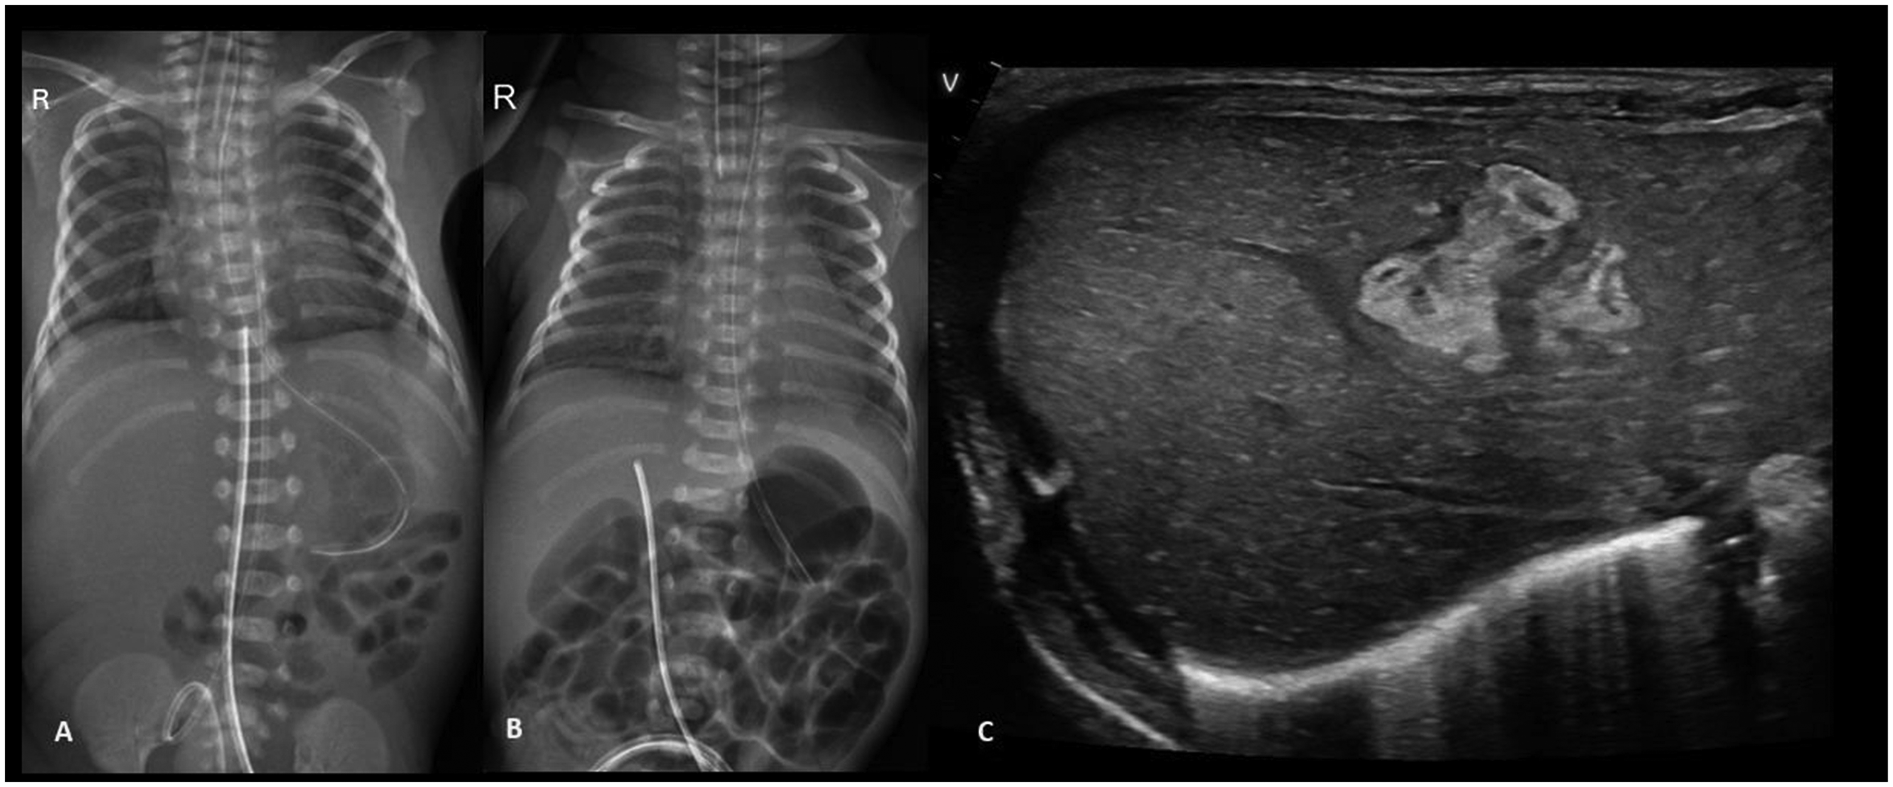

An extremely preterm (27 + 5 weeks), VLBW (1,005 g), male neonate was born to a gravida 2 mother via spontaneous vaginal delivery, with a maternal history of PPROM of 9 h. In the NICU, the neonate received mechanical ventilation and surfactant therapy for respiratory distress within one hour of birth. The UAC and UVC were secured. On check x-ray, the UVC tip was found at the level of the diaphragm, T9-T10 (Figure 5A). First-line antibiotics and TPN were initiated. The neonate was extubated at HOL 24 to NIV support. The UAC was removed on day 3. The infant was reintubated at HOL 70 for worsening respiratory distress on NIV support. A FnECHO was suggestive of a hemodynamically significant PDA and paracetamol was started for PDA closure. A postintubation x-ray incidentally revealed a UVC tip in the liver (Figure 5B), which was adjusted to a low-lying position. The neonate was again extubated on DOL 6 and the UVC was removed on DOL 7. On DOL 9, the baby had abdominal distension associated with bilious aspirates; a sepsis workup showed rising levels of CRP and thrombocytopenia; antibiotics were upgraded further. Blood culture grew Sphingomonas paucimobilis and antibiotics were adjusted as per the sensitivity report. There was clinical improvement, and the neonate remained hemodynamically stable thereafter. On DOL 17, while performing a lung ultrasound for inability to wean NIV support, the neonatal trainee incidentally found a hyperechoic lesion in the right lobe of the liver, measuring 1.4 cm × 1.0 cm × 1.4 cm (Figure 5C). This was confirmed by the radiologist, and a differential diagnosis of liver hematoma or TPN extravasation was considered. The neonate is currently stable on CPAP and full feeds. A follow-up ultrasound on DOL 34 showed regression in the size of a lesion.

Figure 5

Plain chest and abdomen radiograph showing (A) a UVC tip at the level of the diaphragm (T9–10) (B) on day 3, the UVC tip shows migration to the T12 level, likely in hepatic parenchyma (C) liver POCUS showing a heteroechoic mass in the right lobe of the liver.